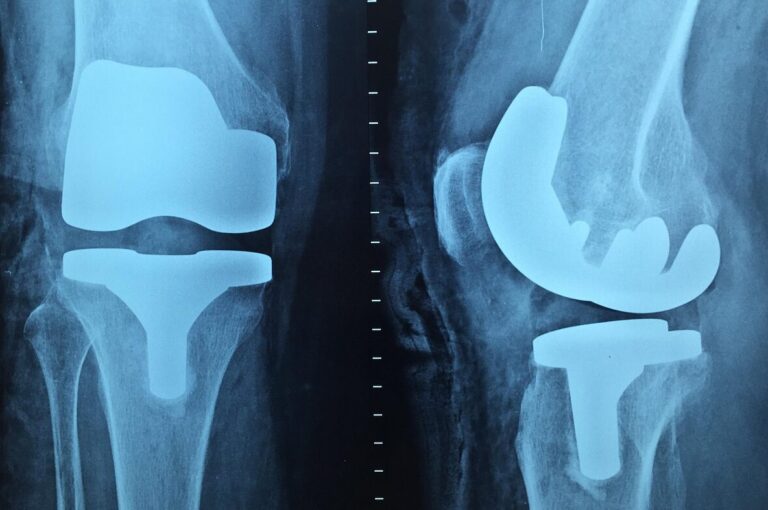

Herstel knieprothese lange termijn: optimaal blijven bewegen na je operatie

Herstel knieprothese lange termijn: optimaal blijven bewegen na je operatie Na de eerste maanden van revalidatie begint een nieuwe fase: het lange termijn herstel.In deze periode draait het niet langer alleen om genezing, maar om het behouden van mobiliteit, spierkracht…